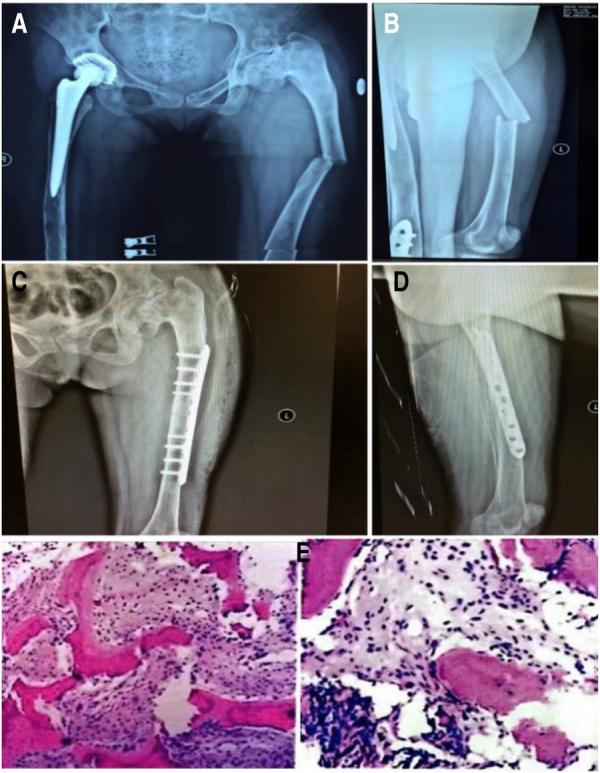

患者2009年至2013年间接受了四次静脉输注唑来膦酸5mg,同时口服补钙。2010年7月进行右侧全髋关节置换术(THA)。术后髋关节X线片见图1。碱性磷酸酶和骨钙素水平分别为538 IU/L和192.5 ng/ml。2013年12月,患者接受了矫形外科手术和右髁上截骨(图2)。入院时,碱性磷酸酶和骨钙素水平为403 IU/L和246.30 ng/ml。2015年5月,患者因跌倒导致左股骨干骨折,并接受了钢板和螺钉内固定(图3)。根据术后组织病理学,最终诊断为纤维发育不良。2015年12月,移除右侧股骨板,以防止应力集中和随后的股骨干骨折。尽管患者在随访期间没有出现明显并发症,但于2017年和2018年在另一家医院接受了颌下感染和下颌骨坏死的治疗(图4)。

图3 轻微外力作用下左股骨干骨折。(A,B)术前x光片,(C,D)术后x光片;(E)术后病理学